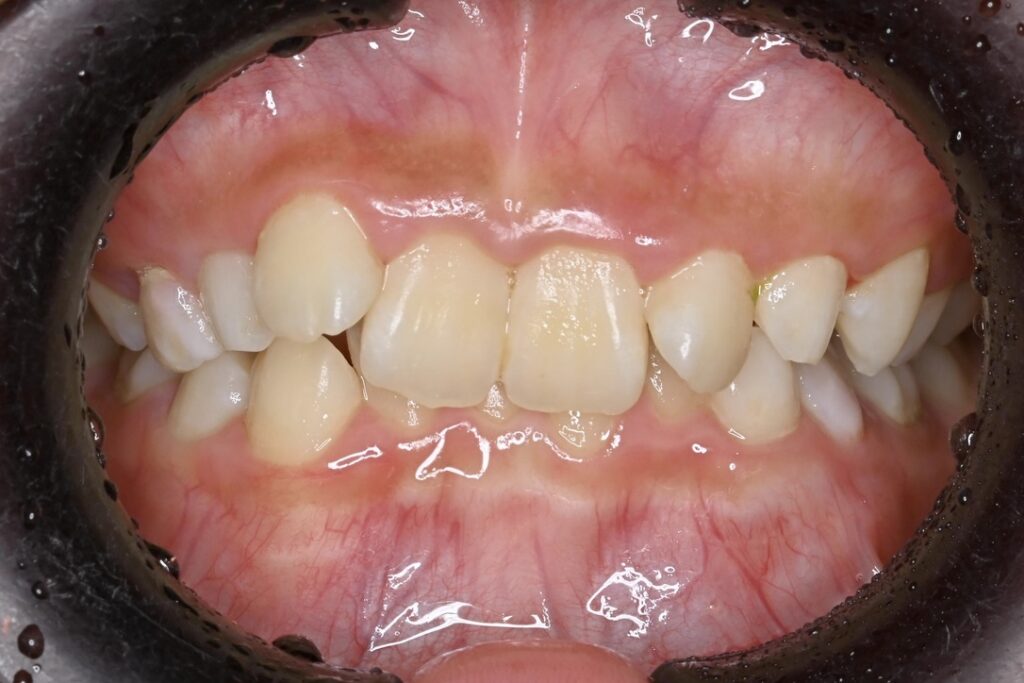

AFTER

主訴 通っている歯医者で矯正した方がいいと言われて気になっている。下の前歯がでこぼこしている。

診断名・主な症状 下顎前歯の叢生を伴う過蓋咬合

治療内容 上下の歯並びの幅を拡げつつ、前歯の関係を改善しました。

使用装置 急速拡大装置

リンガルアーチ

機能的矯正装置(マイオブレース)

抜歯部位 抜歯なし

治療期間 2年 + 後戻り止め期間(3年 )

通院回数 20回

費用 50万円程度(税別)  29331